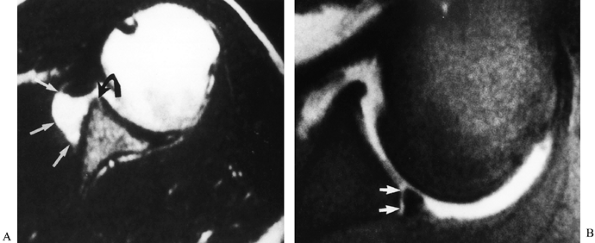

gadolinium has gained great favor, although unfortunately it is often

used as a screening tool in the evaluation of patients. Its role should

instead be to confirm the presence of lesions that may need surgical

management. It is accurate in the detection of labral pathology (Fig. 80.20) (27,56).

Recent advances in MRI technology such as high-resolution fast-spin and

gradient-echo imaging make these methods particularly appealing for

detecting anterior and superior labral injuries (26).

![]() |

|

Figure 80.20. A,B: MR arthrogram demonstrates anterior glenohumeral stripping with an associated Bankart lesion.